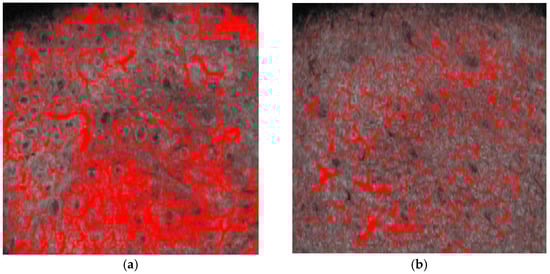

Figure 6.

D-OCT imaging at a depth of 500 microns. Pixel density measurement on horizontal D-OCT 6 × 6 mm image pre- (a) and post- (b) dye laser treatment. The figure demonstrates the reduction of vascular patterns following the application of dye laser treatment.

In our clinical study, we observed significant reductions of vascular density, clinically (Figure 8 and Figure 9), at multispectral analysis (Figure 10) and in OCT, where vascular density at both 300 and 500 microns and collagen density following laser treatment in patients with rhinophyma. The effect sizes for these changes, calculated using Cohen’s d, were substantial, indicating a large and clinically meaningful impact of the treatment. Specifically, the effect sizes for vascular density changes at 300 and 500 microns were −5.19 and −5.63, respectively, while the effect size for collagen density changes was −2.00. (Figure 3) These results highlight the pronounced efficacy of the laser treatment in modifying tissue characteristics associated with rhinophyma. The large effect sizes underscore the treatment’s capability to significantly reduce vascular and collagen densities, aligning with our objectives to alleviate the symptoms and improve the condition of patients suffering from this disorder.

Figure 10.

Multispectral analysis: (a) vascular rhinophyma at baseline; (b) rhinophyma after dye laser and CO2 laser.